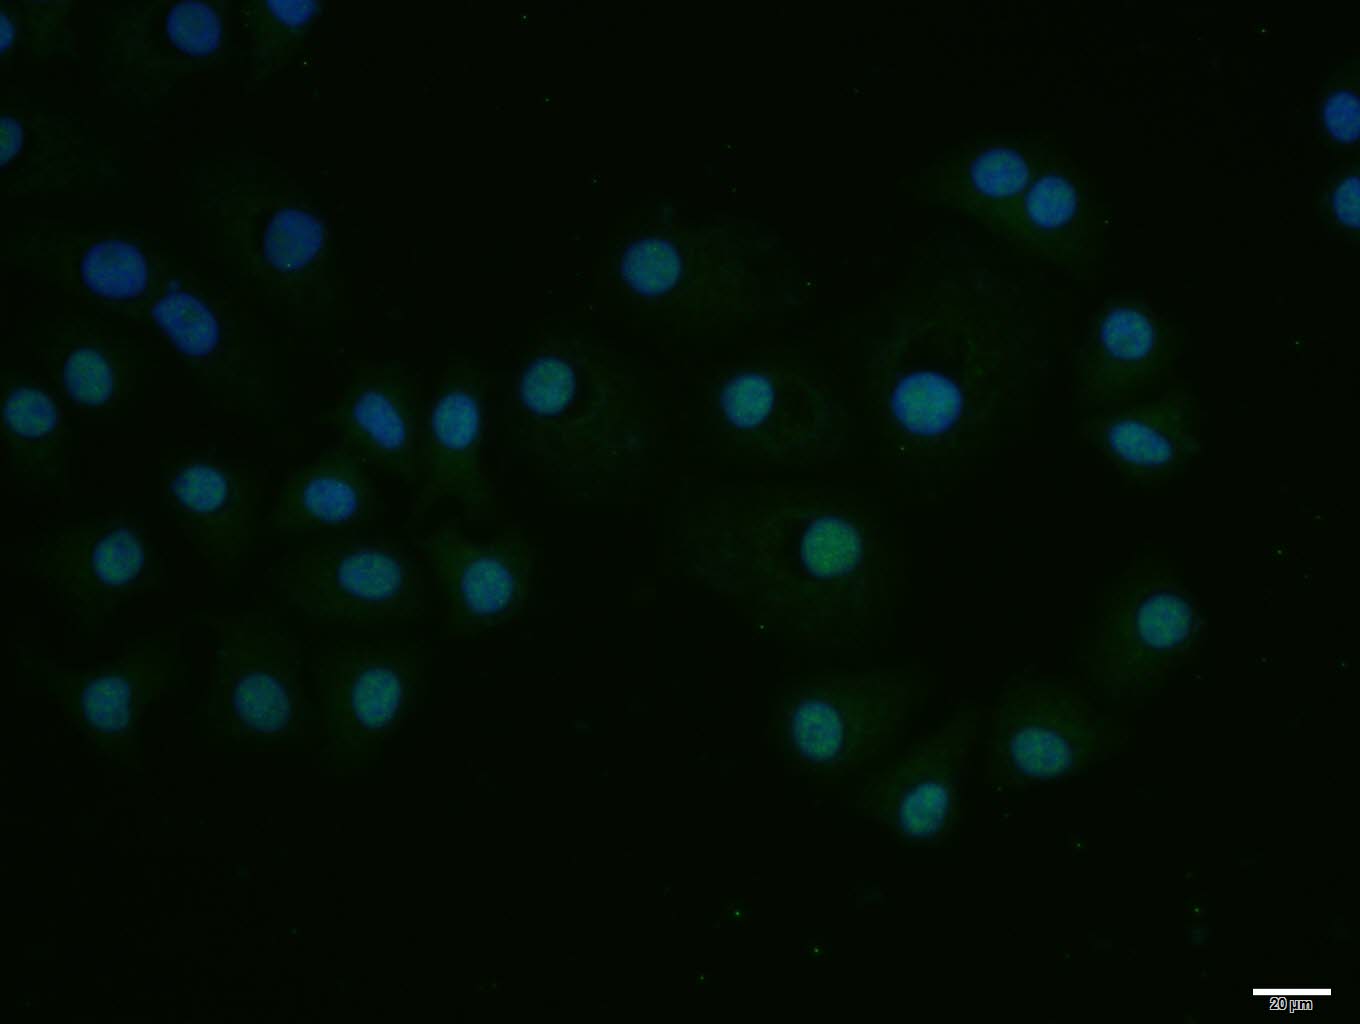

HepG2 cell; 4% Paraformaldehyde-fixed; Triton X-100 at room temperature for 20 min; Blocking buffer (normal goat serum, C-0005) at 37°C for 20 min; Antibody incubation with (E2F1) polyclonal Antibody, Unconjugated (bs-23185R) 1:100, 90 minutes at 37°C; followed by a conjugated Goat Anti-Rabbit IgG antibody at 37°C for 90 minutes, DAPI (blue, C02-04002) was used to stain the cell nuclei.